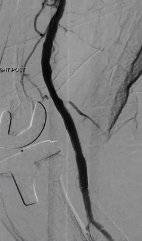

This complex CLI case highlights multilevel treatment in a patient with initial claudication that progressed to rest pain and is successfully treated from an antegrade femoral approach with multiple treatment modalities utilized.

Featuring operator Jihad A. Mustapha, MD, FACC, FSCAI, Advanced Cardiac & Vascular Amputation Prevention Centers; Michigan State University College of Osteopathic Medicine; Grand Rapids, Michigan.